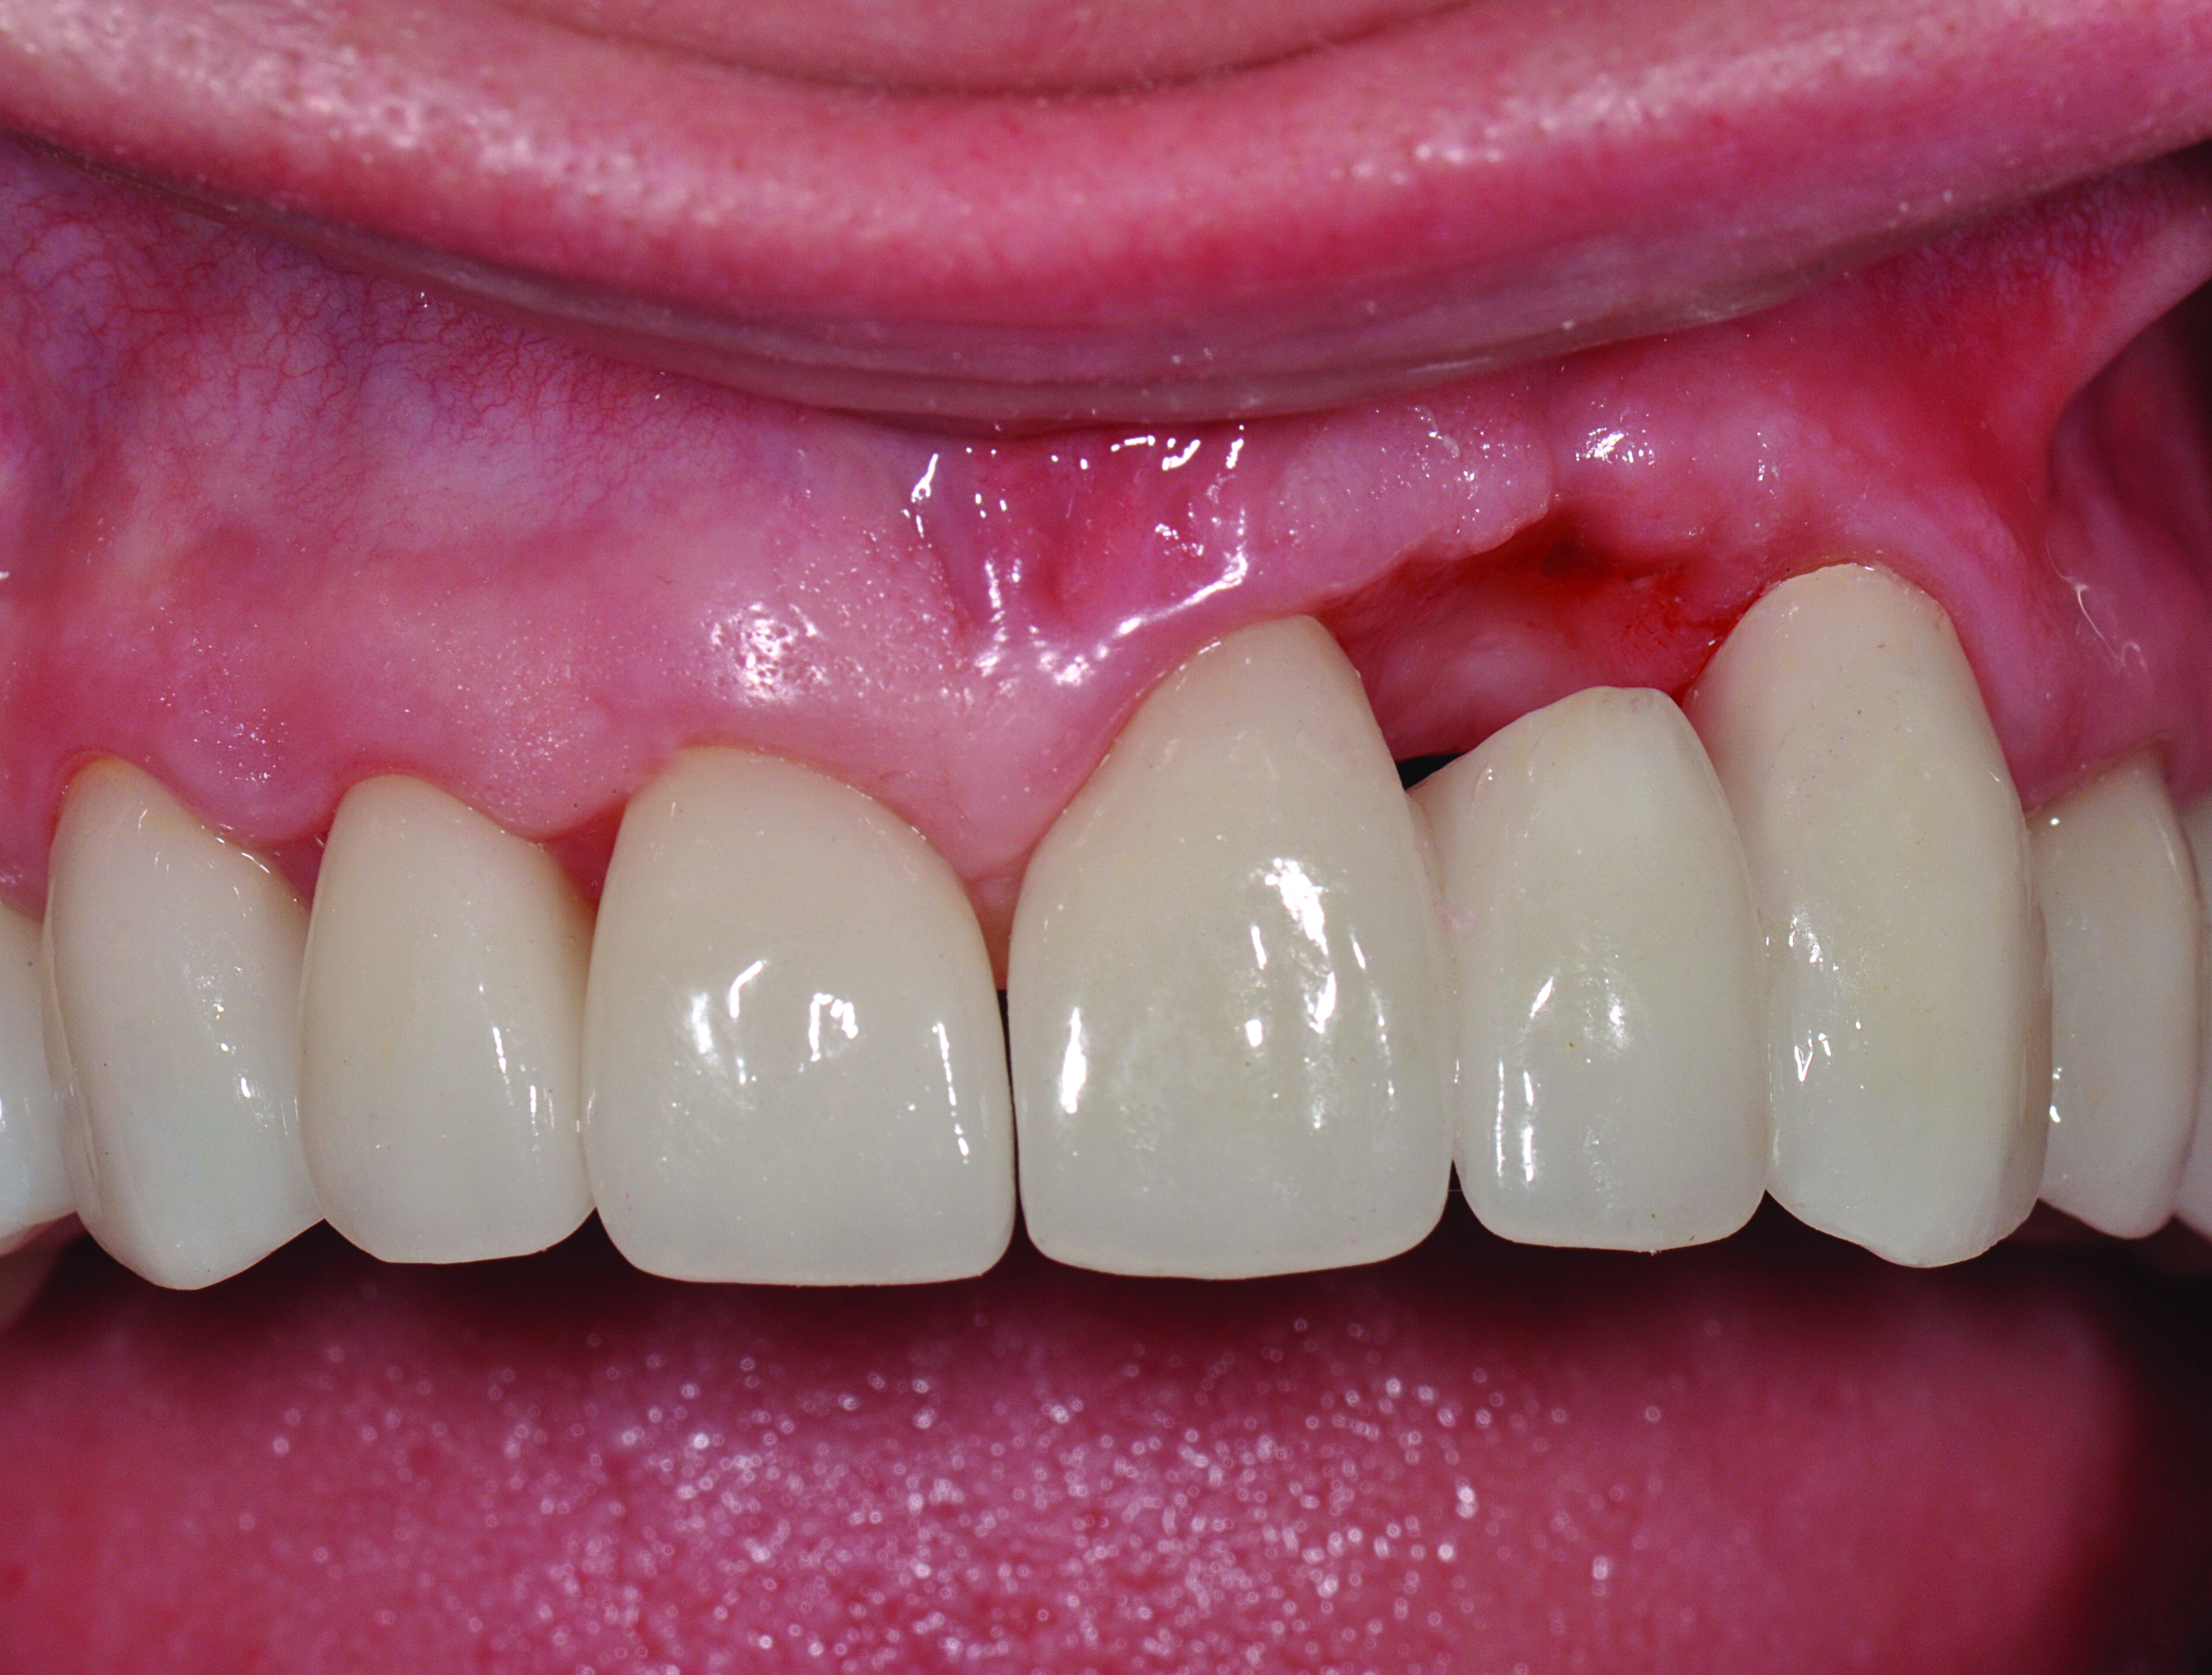

In the final case, adjacent implants were placed in healed sites No. 8 and No. 9 and provisionalized at the time of surgery (Figure 27 and Figure 28). This case illustrates the effect of platform switching on bone and gingival tissue stability, as well as recognizing that appropriate diameter and spacing is important to maintain ideal ridge contour. The gingival tissue anatomy between implants is characteristically shorter than papilla form between adjacent teeth, and, as a consequence, it is important to incorporate implant designs and procedures that minimize bone-level changes and associated soft-tissue recession. The depth of implant placement was subcrestal relative to the ridge crest, based on the future desired free gingival tissue level, while allowing prosthetic running room. The studies of Barros et al and Veis et al noted that implants positioned subcrestally (as seen in Figure 29) showed better crestal bone preservation than those placed equicrestally or supracrestally.28,29 The implant design used in this case achieves excellent primary stability. Along with the optimal 3-dimensional positioning of the implants and, specifically, the subcrestal placement, as well as the immediate provisionalization protocol, these concepts and implants have contributed to a pleasing esthetic outcome, as seen in Figure 30.

Fig 30. Postoperative clinical view, which illustrates good tissue contours interproximally and on the facial of the implants.

Figure 30